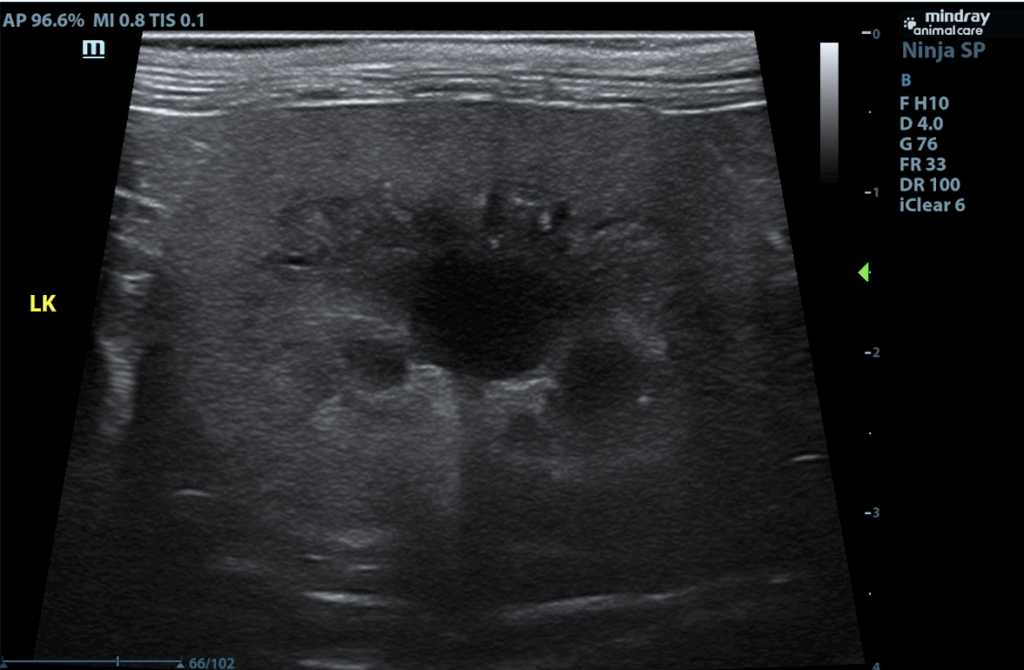

The urinary bladder is adequately distended with anechoic contents. No masses, inflammatory changes, echogenic sediment or cystoliths are observed. The urinary bladder, trigone and visible pelvic urethra are normal in thickness with a smooth mucosal surface. Kidneys are normal in size and contour. A relatively uniform hyperechogenicity is observed with mildly decreased corticomedullary distinction. There is no pyelectasia noted and no mineral is observed. No overt masses/nodules are observed. The left kidney measures 4.19 cm. The right kidney measures 4.33 cm.

The right adrenal gland is normal in size (0.38 cm at cranial pole and 0.31 cm at caudal pole), shape and overall architecture, echogenicity and echotexture. Visible surrounding vasculature appears normal. The left adrenal gland is enlarged, measuring 1.8 cm long x 1.2 cm thick at the caudal pole, with mild heterogeneous parenchymal changes and an overall egg-shaped hypoechoic appearance, with swollen capsular expansion noted but no evidence of capsular escape or vascular invasion.